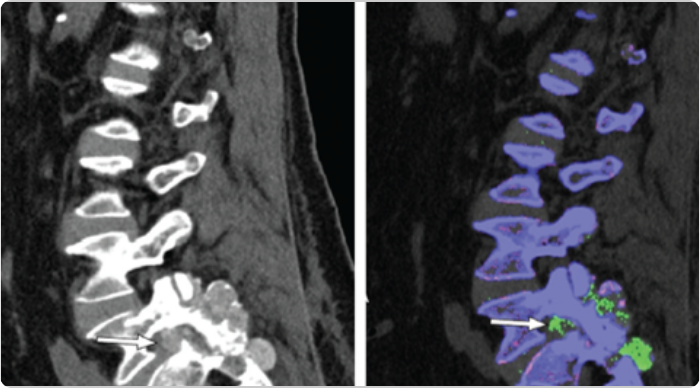

DECT scans of lumbar spine showing tophaceous deposits

Sagittal mixed 120-kVp equivalent images of lumbar spine obtained with dual-energy CT demonstrate an intermediate-attenuation mass in the L5-S1 facet joint with bony erosions and narrowing of the neural foramen (arrow, left). Dual-energy material labeling color map overlay shows monosodium urate (green) and bone (blue and pink). Note the monosodium urate crystals crowding the left neural foramen (arrow, right).3

Adapted from Gibney B, et al. Radiology. 2020;296:276.

KRYSTEXXA has not been studied to reverse damage to the spine or any of the body's organ.

CT, computed tomography.